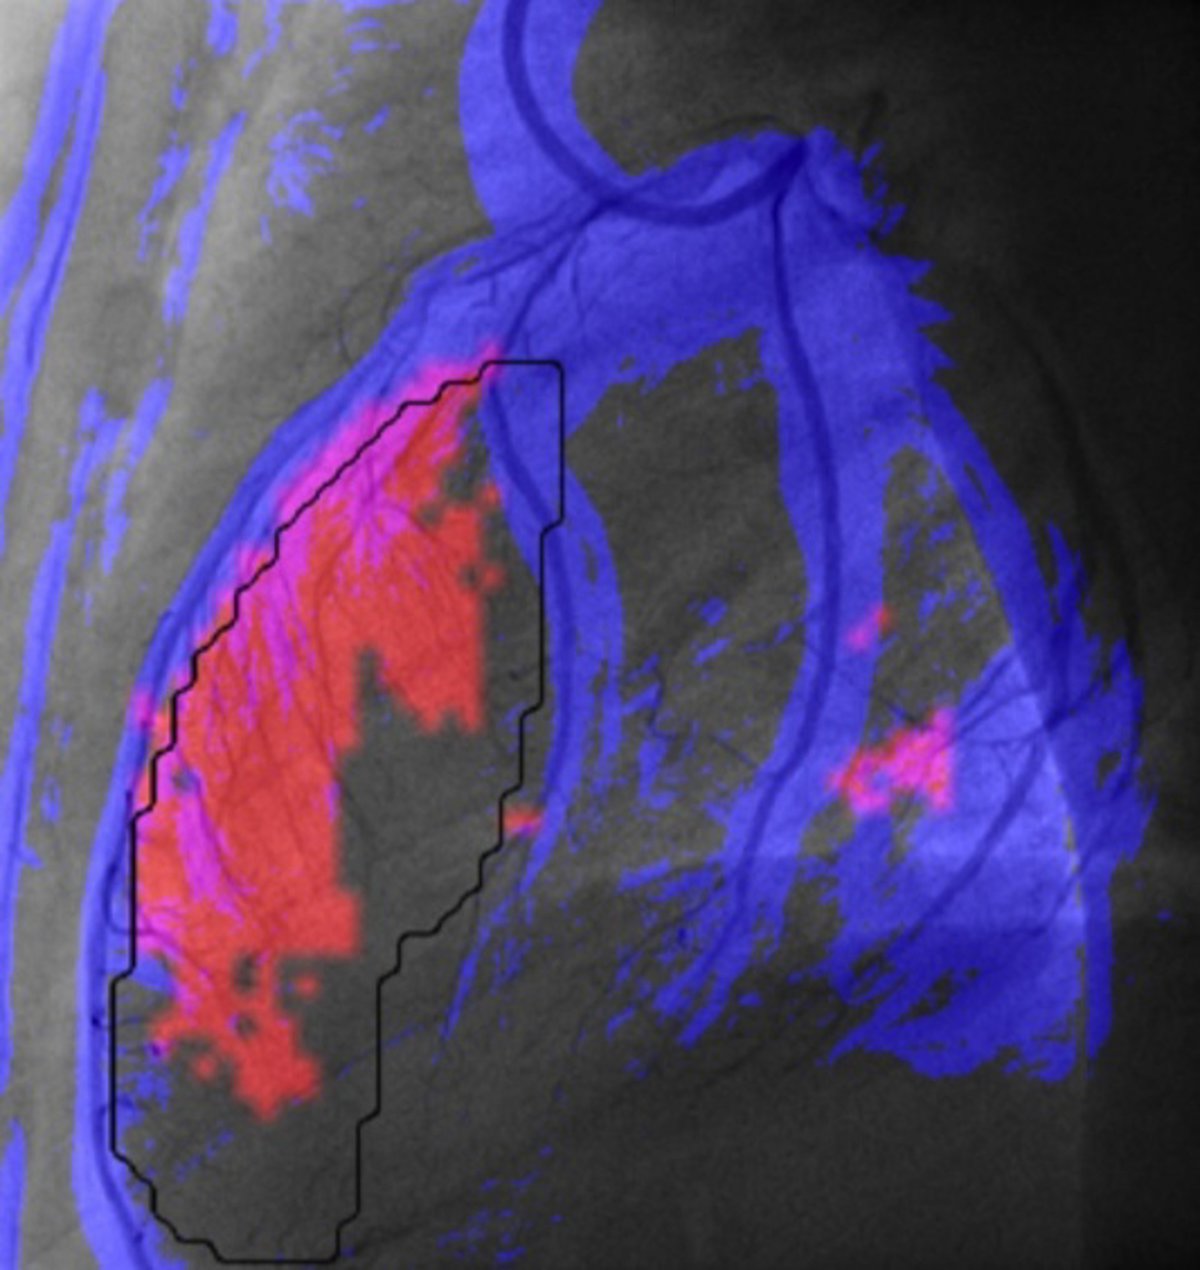

Programa informático para mejorar el diagnóstico de daño cardíaco por un infarto

CVC/UAB

Investigadores del Centro de Visión para Computador (CVC) de la Universitat Autònoma de Barcelona (UAB) han diseñado una herramienta informática para mejorar y agilizar el diagnóstico de daño cardíaco después de sufrir un infarto.

A través del análisis de imágenes, la herramienta permite obtener una medida "cuantitativa, reproducible y más objetiva" de la irrigación miocárdica; identifica las regiones con menor riego sanguíneo, y facilita la comparación rápida entre los estados de antes y después de la operación, y entre dos arterias.